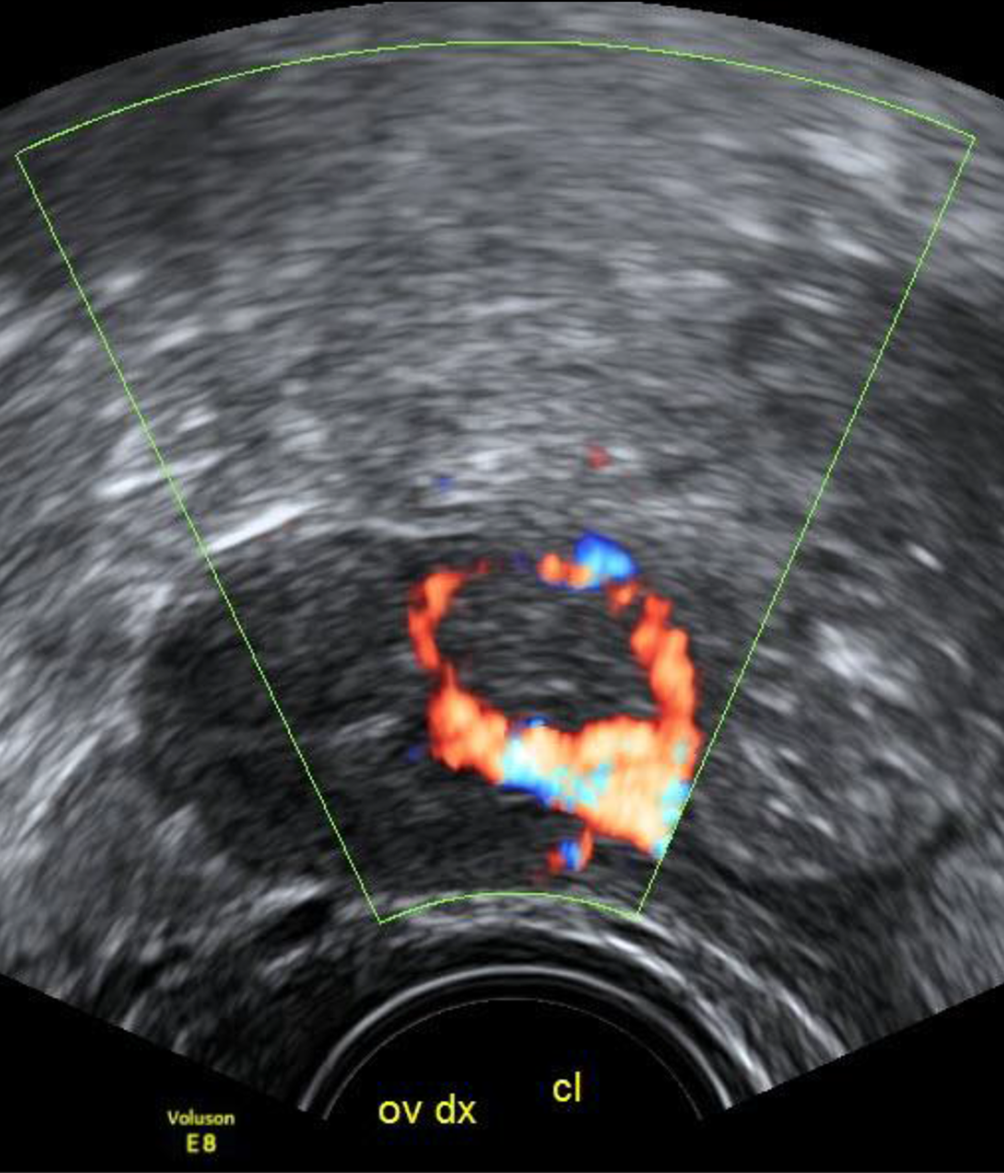

Abb. 1

Ein von Erscheinungsbild und Echodensität nicht vom restlichen Ovar zu unterscheidendes Corpus luteum zeigt sich im Farbdoppler durch die markante zirkuläre Vaskularisation, den „ring of fire“

Sehr hilfreich ist der Farbdoppler bei der Feststellung eines Corpus luteum – die für die endokrine Aktivität des Organs nötige periphere Vaskularisation zeigt sich in einer meist kreisrunden, 1–2 cm großen charakteristischen Struktur im Ovar – im Ultraschalljargon, seit es den Farbdoppler gibt, als „ring of fire“ bekannt. Diese Vaskularisation nimmt rund 10 Tage nach der Ovulation ab, mit Beginn der Monatsblutung ist sie kaum mehr vorhanden. Solide Strukturen im Inneren der Flüssigkeit kann man nur dann sicher als Koagel beschreiben, wenn sie im Farbdoppler nicht vaskularisiert sind. Wären die echodensen Strukturen innerhalb der Flüssigkeit in Abb. 4 vaskularisiert, müsste die Verdachtsdiagnose auf ein Muzinkystom oder ein Malignom lauten und der Befund müsste nach den IOTA-Kriterien beurteilt werden [1].